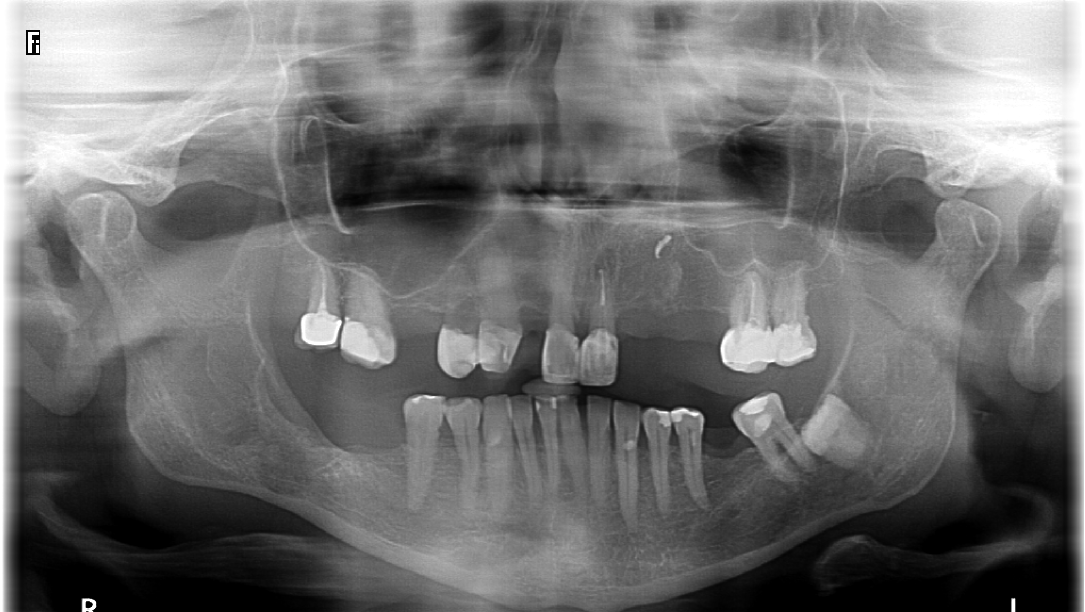

Po 6 miesiącach od zabiegu w badaniu klinicznym nie stwierdzono dolegliwości bólowych, a w badaniu pantomograficznym obserwowano gojenie loży po wyłuszczonej torbieli (ryc. 3).

Ryc. 3. Kontrolne badanie pantomograficzne wykonane 6 miesięcy od zabiegu – widoczne gojenie kości po stronie prawej (maj 2021).

Na kolejne badanie kontrolne pacjentka zgłosiła się po 1,5 roku od zabiegu. Nie zgłaszała żadnych dolegliwości bólowych. W badaniu klinicznym stwierdzono ciągłość blaszki zbitej gałęzi, trzonu i kąta żuchwy po stronie prawej. Wykonano badanie CBCT, które wykazało prawidłowe utkanie tkanki kostnej w obrębie gałęzi, kąta i trzonu żuchwy (ryc. 4 i 5).